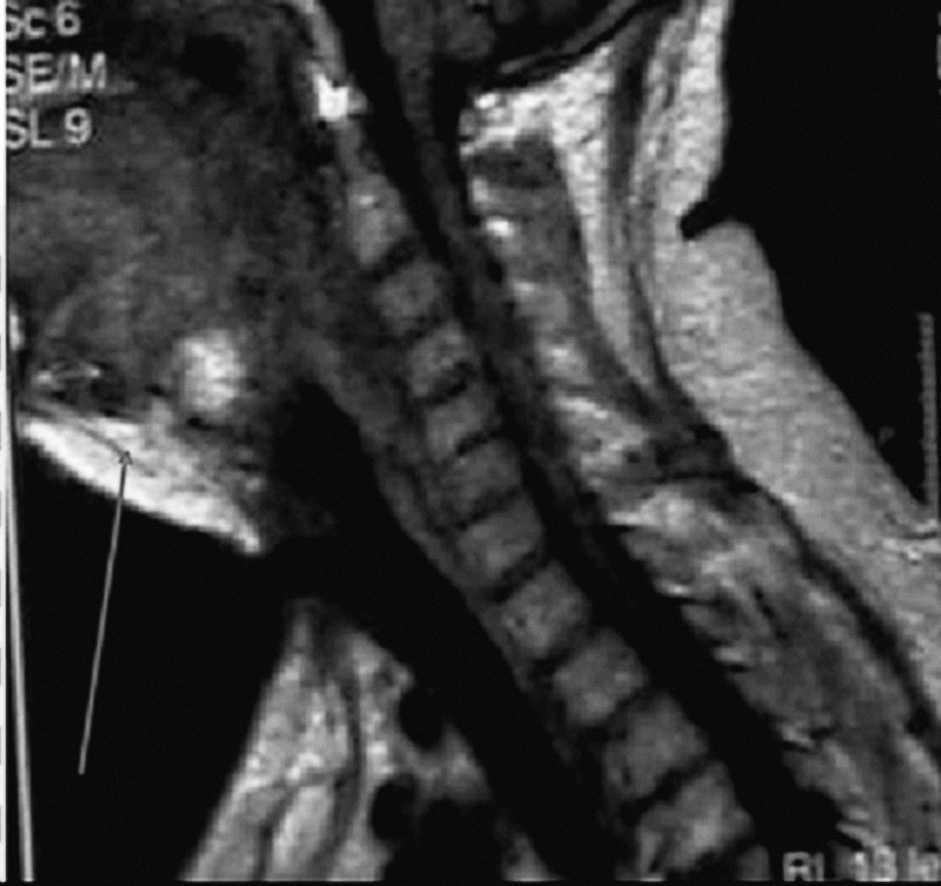

A los 13 meses de la intervención, el paciente acudió de nuevo a nuestro hospital por notarse una tumoración cervical y disnea a pequeños esfuerzos. A la exploración destacaba una tumoración submandibular derecha dura, adherida a planos profundos, de aproximadamente 3 x 4 cm de diámetro. La resonancia magnética puso de manifiesto una tumoración orofaríngea y nasofaríngea, con obliteración del espacio aéreo (fig. 2). Mediante biopsia incisional, se confirmó histológicamente que dicha lesión correspondía a un foco extrapulmonar del seudotumor (fig. 3). El tumor se comportó de forma agresiva infiltrando la porción cervical del esófago y la vía aérea, clínicamente manifestada como disfagia e insuficiencia respiratoria, por lo que requirió la realización de gastrostomía y traqueostomía permanente. En posteriores radiografías de control se detectó la aparición de nuevas masas pulmonares, una localizada en el lóbulo superior izquierdo y otra paramediastínica derecha. Se desestimó la opción quirúrgica y se inició tratamiento farmacológico con corticoides e inmunosupresores; el paciente respondió al tratamiento y se objetivó una disminución del tamaño de sus procesos tumorales.

Fig. 2. Resonancia magnética que muestra tumoración orofaríngea y nasofaríngea, con obliteración del espacio aéreo.